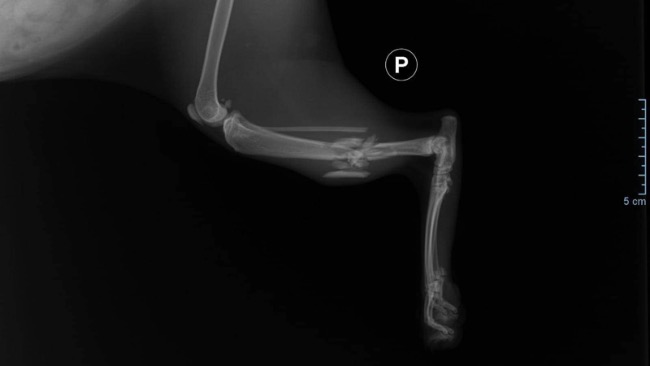

Jej łapka jest złamana, mamy szansę ją uratować by mogła odzyskać sprawność - potrzebna jest pilna operacja.

Łapa Bajki wisi bezwładnie od kolana w dół. Konieczne jest ustabilizowanie jej na płytce.